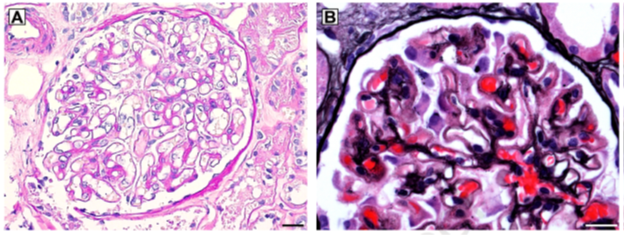

Histologically, NELL1 MN cases have prominent capillary loops with formation of spikes and holes on silver stains as we would expect. There were no proliferative changes, such as those seen in lupus nephritis. 7/21

What sets NELL1 apart is that there is segmental to incomplete global IgG staining on immunofluorescence. This allows us to pick out these cases from other membranous cases. 8/21

Here’s electron microscopy showing a capillary loop spared of deposits, adjacent to one with deposits, demonstrating this segmental nature of immune deposition. 9/21

This pattern is not seen in other types of membranous, including PLA2R, THSD7A, or EXT1/2 associated MN. 10/21